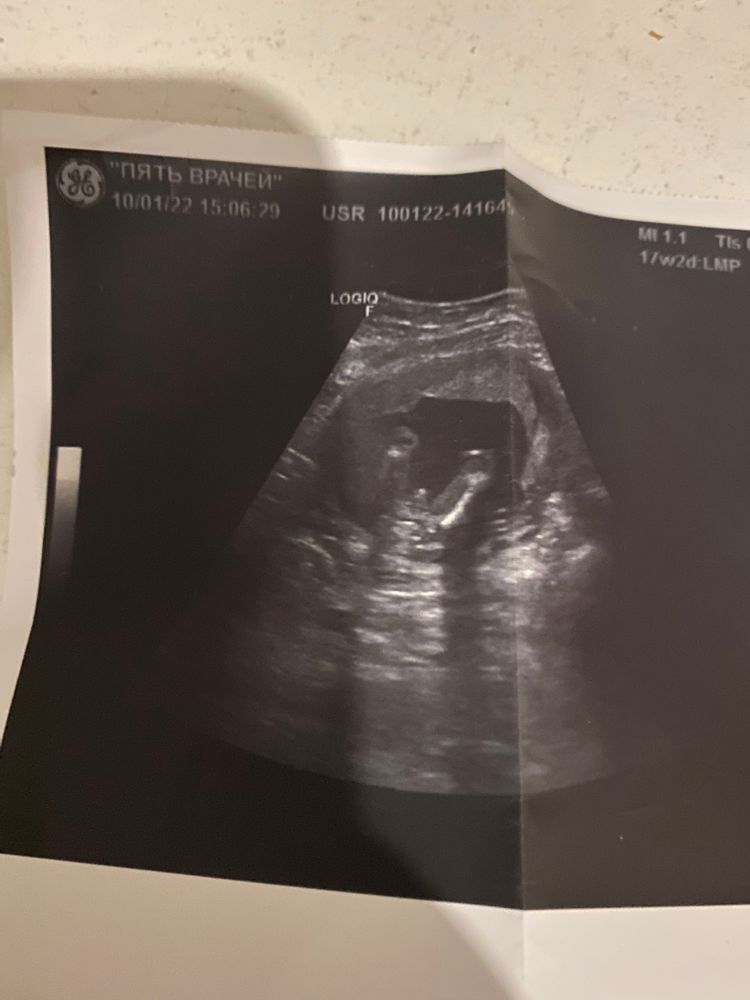

Как думаете, кто будет?

Видно же, что мальчик))) Вам не сказали?

Юлия *, она сказала, но гарантии нет говорит, просто я не вижу яичек на фото, как у других посмотрела , там все четко видно, а тут просто бугорочек

Юлия Сочинская, ну так яички позже спускаются в мошонку, вот их и нет)))

Парень. Разве могут быть сомнения?)) Чёткое хорошее фото.

Смотря какой срок, если 10-11 недель, то так не смотрят. А вот после 14 и дальше, то тут мальчик однозначно

Таня, 17,2 срок на фото, но врач так долго пыталась посмотреть, потому что ребёнок прятался , вот и думаю может этот бугорок , совсем нет то 🙈

Мальчик. Это какой срок?

Елена, 17,2 срок на фото

Однозначно мальчик,у девочек такой пипки нет😂😂